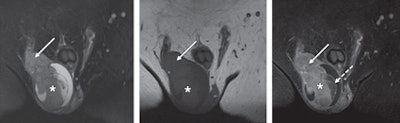

| A 66-year-old man with right-sided seminoma (asterisk), correctly localized and characterized with MRI. Coronal T2-weighted fat-suppressed (left), T1-weighted (center), and T1-weighted fat-suppressed contrast-enhanced (right) MR images show multinodular configuration with enhancing septa of mass and infiltration of tunica albuginea, epididymis, and spermatic cord (solid arrow). Noninfiltrated part of testicle has necrotic nonperfused parenchyma after contrast enhancement (dashed arrow). Images courtesy of AJR. |

The individual pattern of the 28 testicular lesions was correctly analyzed as cystic, solid, mixed, edema, hemorrhagic, or tunical involvement in all cases. Once again, sensitivity, specificity, NPV, and PPV were 100%.